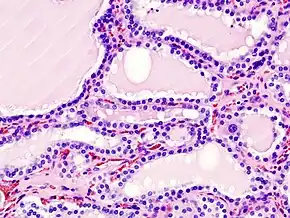

.jpg)